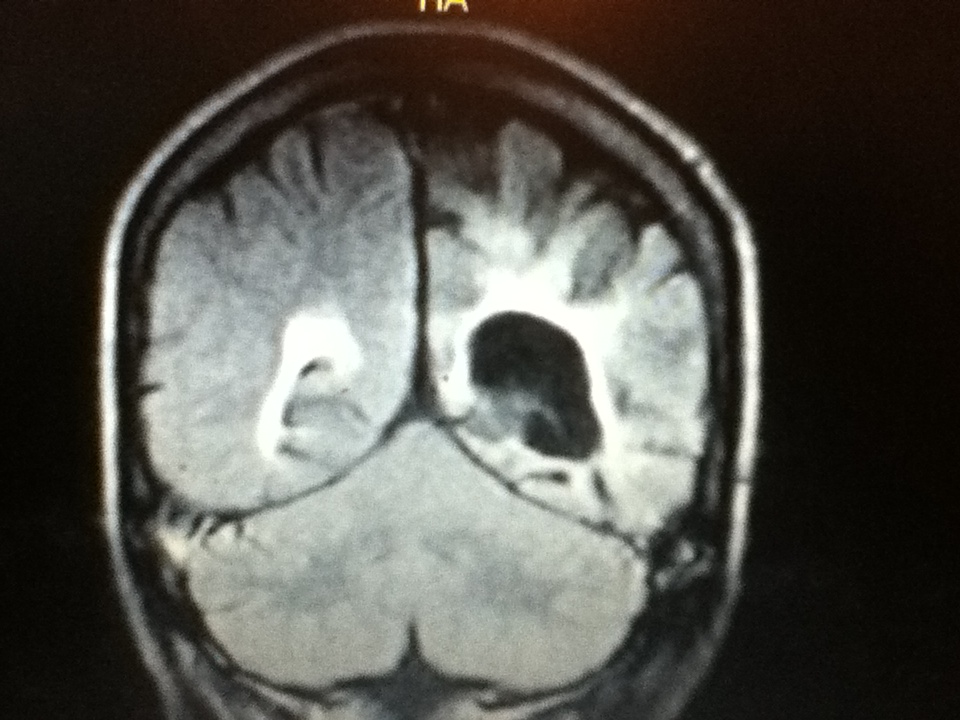

From rad-log.blogspot.com

HIV encephalopathy and AIDS dementia complex Hiv Brain Atrophy People living with hiv are affected by the chronic consequences of neurocognitive impairment (nci) despite antiretroviral. Early treatment with antiretroviral drugs can change the trajectory of neurological complications of hiv infection and prevent. This activity reviews the epidemiology, etiology, clinical signs and symptoms, evaluation, and treatment of. Additionally, processes associated with cognitive disorders in hiv, including neuroinflammation, 24,25 brain atrophy,. Hiv Brain Atrophy.